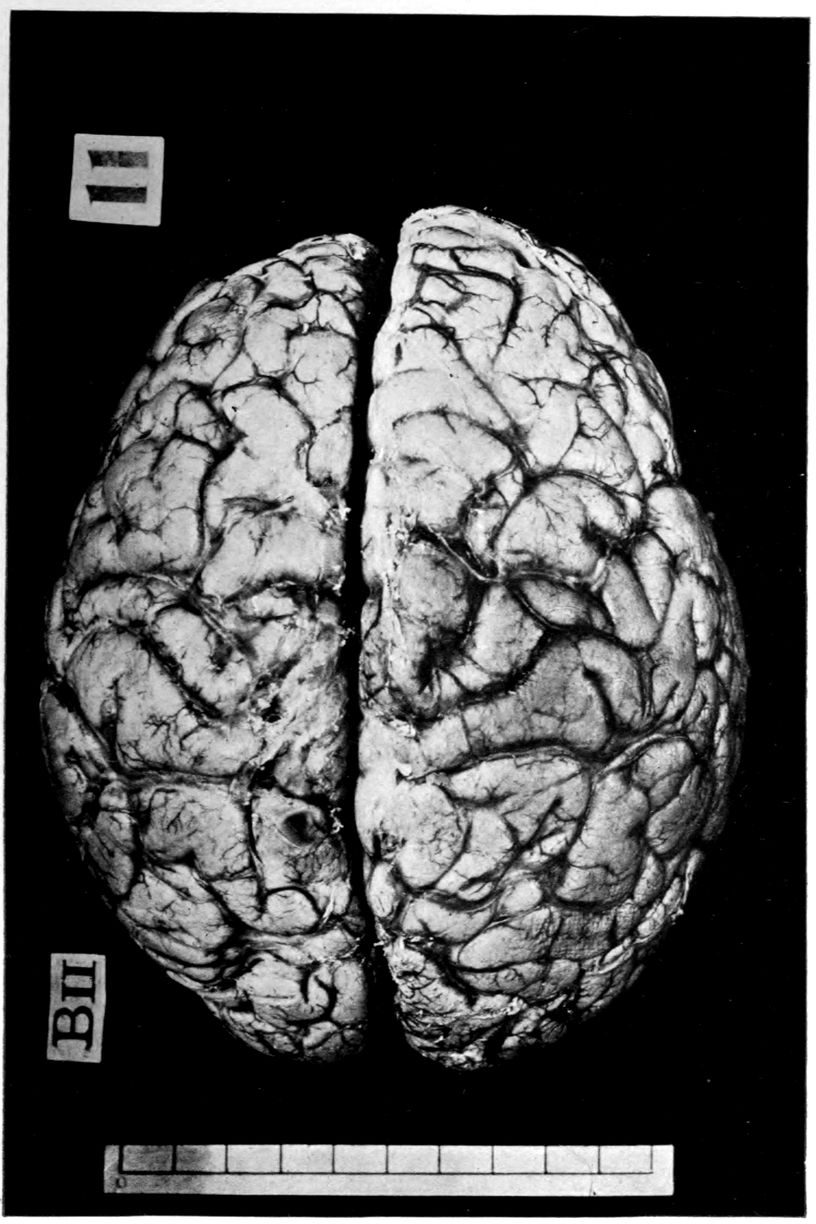

The calvarium was dense and the dura mater thick and adherent. There was a chronic leptomeningitis, which, however, was rather unusual in being most marked in the posterior cisterna and along the sulci of the cerebellar hemispheres. There was a general cerebral sclerosis, with a question of atrophy of the superior temporal gyri (suggesting the so-called Lissauer’s paresis). There was a marked cerebellar sclerosis with a consequent sclerosis (grossly palpable) of the commissural fibres of the pons. There was a generalized slight spinal sclerosis. As a fair sample of the variety of head findings in paretic neurosyphilis, the details of the head examination are presented.

39Crown bald, with a slight fuzzy growth of short hairs. Scalp slightly adherent to calvarium; latter of usual thickness but denser than normal. Dura adherent to calvarium in region of vertex; dura not remarkable. Sinuses normal. Arachnoid villi moderately developed. Pia mater a trifle thickened and rather evenly throughout the cerebral portion. Linear sulcal markings are remarkable for their absence. The wall of the cerebellomedullary cisterna is thick and opaque. The most prominent pial thickenings are over the cerebellum. These are linear or may show feathery out-growths and are seated over the sulci, particularly in the neighborhood of the fissure and about the great cerebellar notch. They correspond fairly well with the focal variation in consistence of underlying tissues noted below.

Brain weight, 1265 grams. Consistence somewhat increased throughout and somewhat evenly increased. The prefrontal region shows the maximal increase of consistence but the remainder of the frontal region and corresponding occipital region are much firmer than normal. The two superior temporal gyri appear to be firmer than adjacent gyri and are possibly slightly diminished in superficial diameter. The hippocampal gyri are fairly firm. The substance on section is a trifle more moist than normal. The gray and white matter cut quite evenly. Diminution in depth of gray matter, if existent, could not be demonstrated. The ventricles show a moderate sanding throughout, best marked in the fourth ventricle. The basal ganglia are not remarkable except for the development of numerous dilated perivascular spaces about the lenticulostriate vessels. The pons is atrophic, but more so on the right side. The pons, like the prefrontal cortex, shows on section a distinct increase of consistence immediately beneath the pia mater. The white bands of the pons on section are distinctly firmer than the intervening substance. The olives are of equal consistence. Weight of cerebellum, pons, and medulla, 155 grams. The cerebellum shows an obvious atrophic and gliotic process of a symmetrical character. The superior surface, including both vermis and hemispheres, shows a consistence above normal and general reduction of the depth measured from the white matter. The reduction in depth gives rise to a visible depression as compared with tissue posterior to the postclival sulci. The lobus cacuminis, though slightly raised from the surrounding lobes, is equally firm, if not firmer. The superior and inferior surfaces show practically an equal increase of consistence. The dentate nuclei are not especially increased in consistence. The flocculi are reduced in size about one-third.